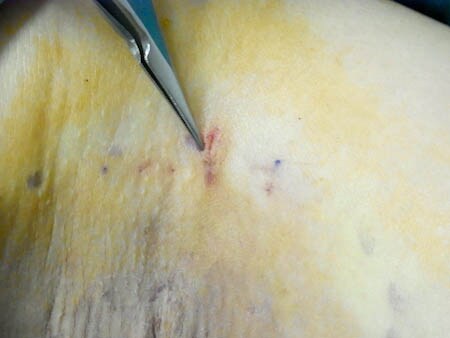

皮膚一枚。ペラッペラですね。 アポクリン汗腺が根こそぎ除去されていることを意味しています。 傷についても見てみましょう。

拡大して見てみましょう。

徹底的にアポクリン汗腺を根こそいでも

傷はわずか。

シワに沿って作るので目立つこともありません。